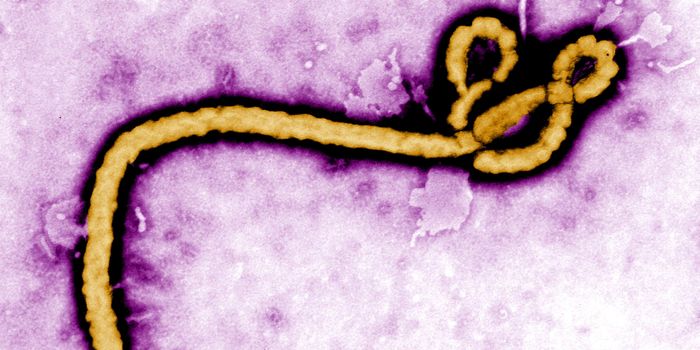

SEP 22, 2014ImmunologySixty percent of those infected in Africa die within eight days to three weeks after contracting the Ebola virus. But so ...